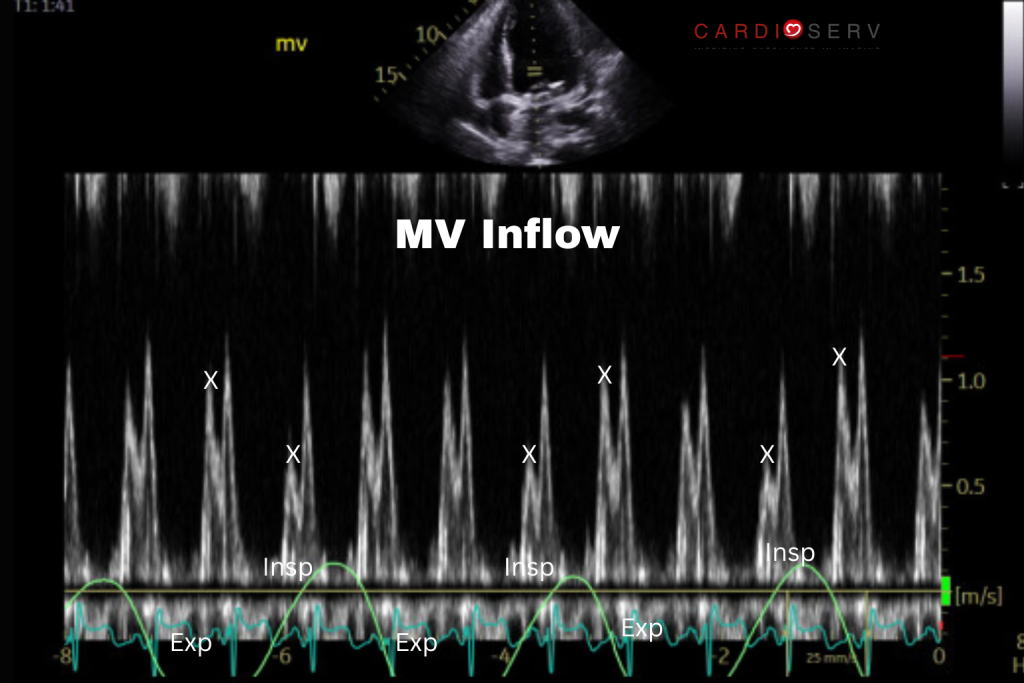

Mitral Valve Inflow

>30% decrease in peak E wave velocity with inspiration, increase with expiration.

How to Evaluate Respiratory Variation

Technique:

- View: Apical 4-chamber

- Mode: Pulsed-Wave Doppler

- Cursor position: At leaflet tips, parallel to flow

- Sweep speed: 25-50 mmHg (slow)

- Respiratory cycle: Label inspiration/expiration; record ≥3 full cycles